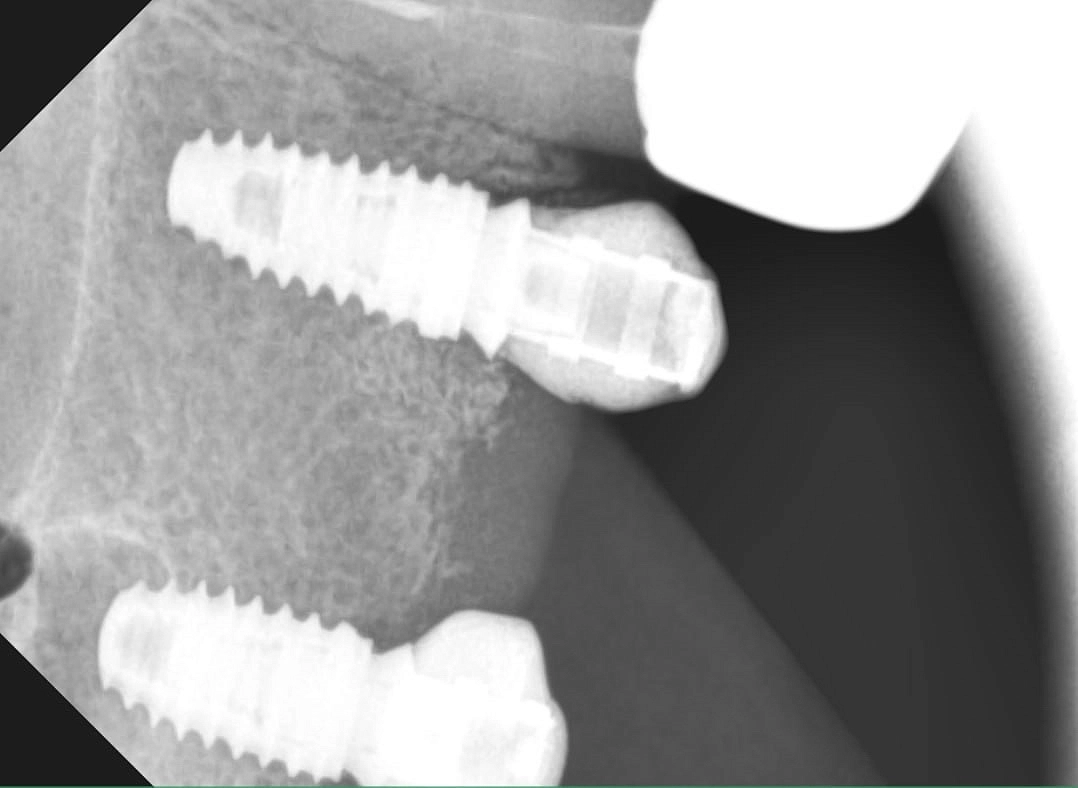

Федотов Руслан Валерьевич – высококвалифицированный стоматолог-хирург с более чем десятилетним стажем работы, который посвятил свою профессиональную деятельность помощи людям в достижении здоровой и красивой улыбки. За время своей практики он успешно освоил и внедрил в работу множество современных методик и систем имплантации, что позволяет ему находить индивидуальный подход к каждому пациенту, учитывая все особенности и потребности.

В своей работе Руслан Валерьевич использует только современное оборудование и материалы, соответствующие международным стандартам качества. Он мастерски владеет различными методиками имплантации, включая одноэтапные протоколы и компьютерную навигацию. Особое внимание врач уделяет безболезненности процедур и комфортному восстановлению пациентов после операций.